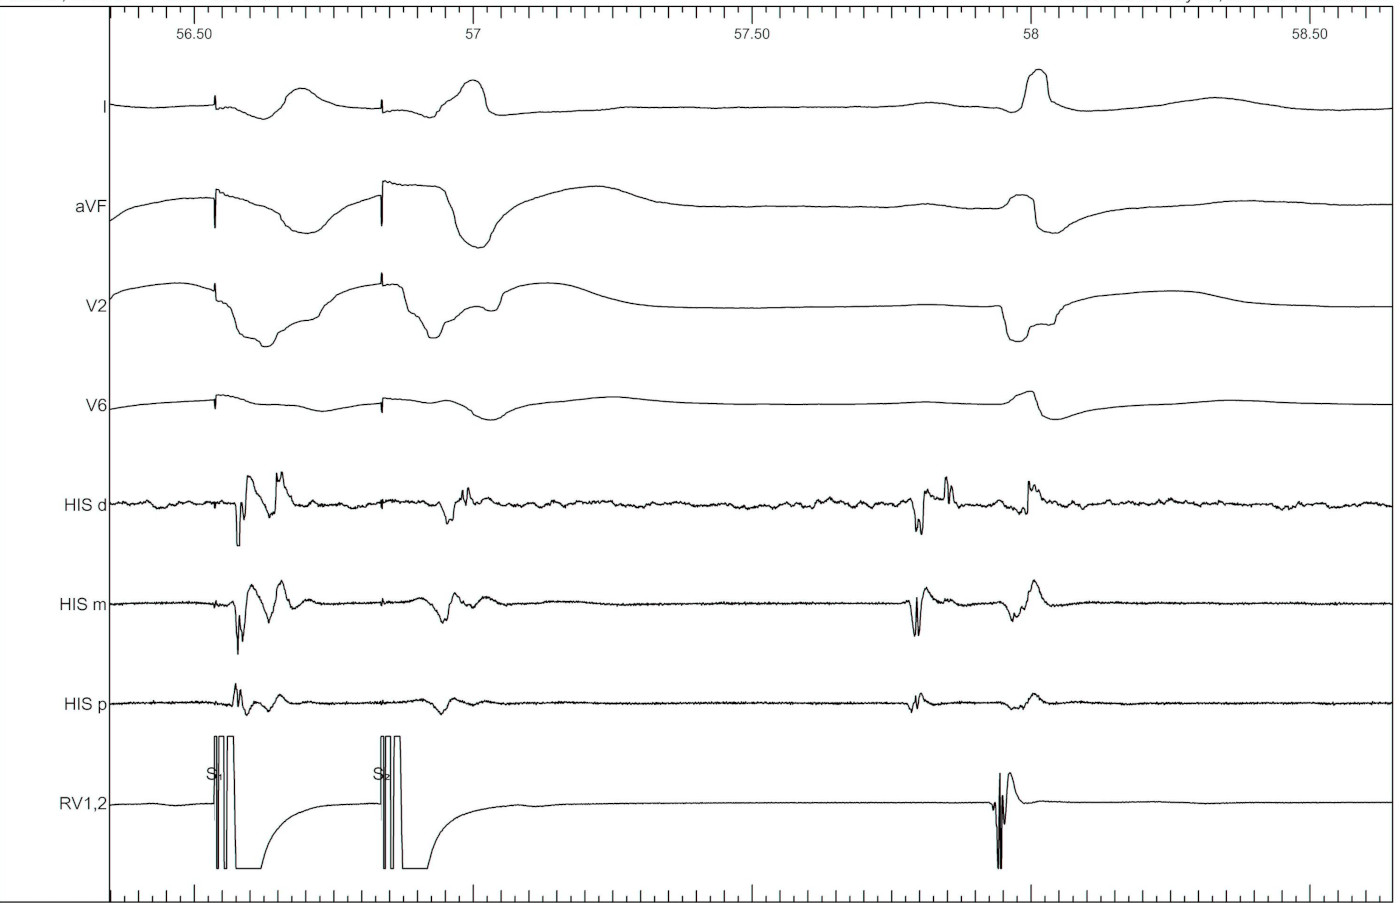

RV 400/500/280

03_rv_400_500_280.jpg

RV 400/500/260

04_rv_400_500_260.jpg